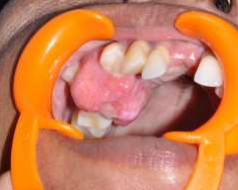

Regional lymphnodes were non palpable. A thorough intra-oral examination revealed a firm, rubbery, reddish pink sessile mass in the maxillary right first and second premolar region measuring 3 × 4 mm in size, oval with diffused borders [Figure 2].

Figure 2: Intra-oral Lesion

The surface of the lesion was smooth. The second premolar drifted buccally [Figure 3].

Figure 3: Migrated 2nd premolar on buccal aspect of the lesion.

The mass was firm in consistency; non tender and no bruit or pulse was felt. Considerable deposition of sub and supragingial plaque and calculus and grade I mobility in relation to first and second premolar was noticed. The lesion was painless unless traumatized by aggressive tooth brushing or chewing hard foodstuffs.